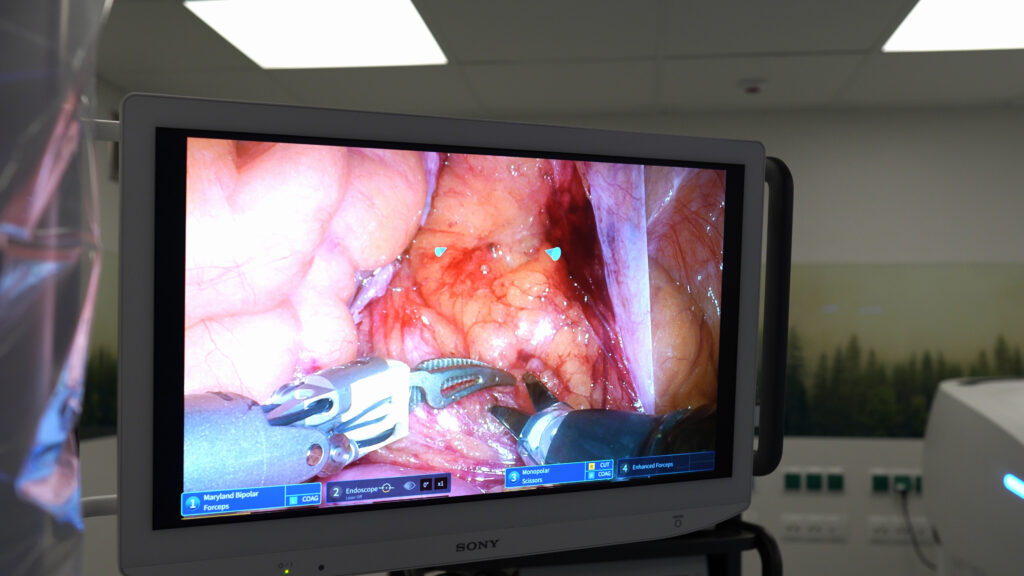

Lek. Karol Sasim oraz lek. Antoni Górczak przeprowadzili w Kościerzynie dwa zabiegi prostatektomii radykalnej w asyście własnego robota chirurgicznego Edge Medical MP1000. Zespoły operacyjne zostały doskonale wyszkolone w technikach laparoskopowych, a wdrożenie robota chirurgicznego stanowi następny etap ich rozwoju. Dzięki zastosowaniu technologii dual console chirurdzy zyskali unikatową w skali kraju możliwość wspólnej pracy podczas zabiegów oraz prowadzenia edukacji młodych adeptów.

17 listopada w Szpitalu Specjalistycznym w Kościerzynie przeprowadzono pierwszy zabieg w publicznym ośrodku w Polsce na własnym robocie Edge Medical MP1000. To przełomowe wydarzenie dla polskiej medycyny i ważny krok w rozwoju technologii chirurgii wspomaganej robotycznie w sektorze publicznym.